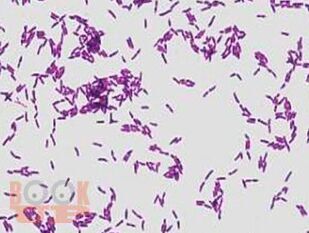

Неспорообразующие возбудители анаэробных инфекций

В пособии изложены современные сведения о систематике, морфологических, культуральных, биохимических и физиологических свойствах, экологии неспорообразующих анаэробных бактерий, а также их роли в медицине.